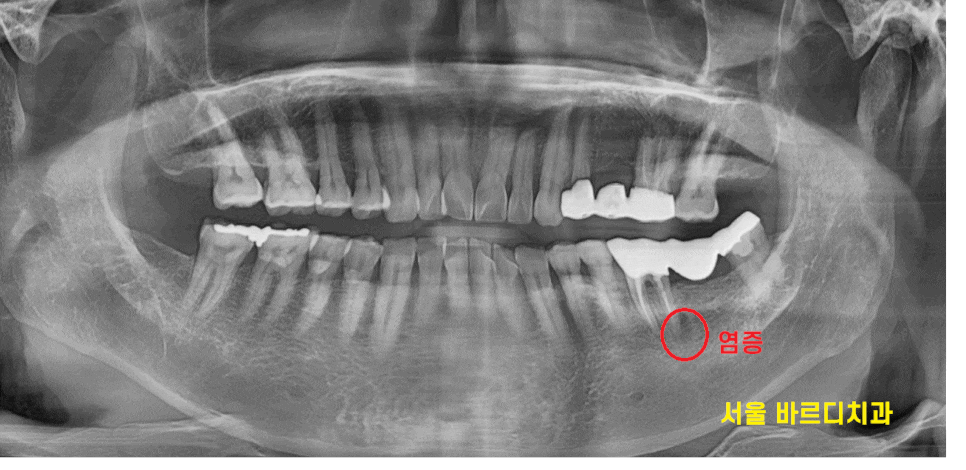

예전에 치료한 부위가 아프다고 하신 환자분

x-ray를 찍어 보니

왼쪽 아래 씌운 치아 뿌리 끝에 농양이 보입니다.

염증이 있으니 씌운 치아 통증 있을 수 밖에요

23.06.27